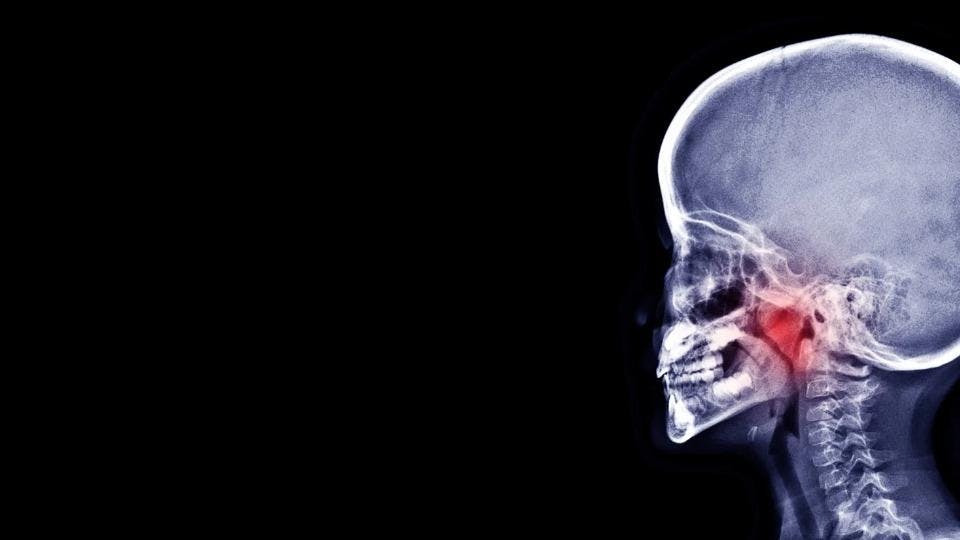

Adenoid terletak dibagian dalam, yang hanya dapat dilihat menggunakan metode Nasofaringoskopi atau Radiografi Nasofaring Lateral (Rontgen). Setiap manusia dilahirkan dengan adenoid, dan ukurannya memang paling besar saat anak berusia sekitar 3 hingga 5 tahun.